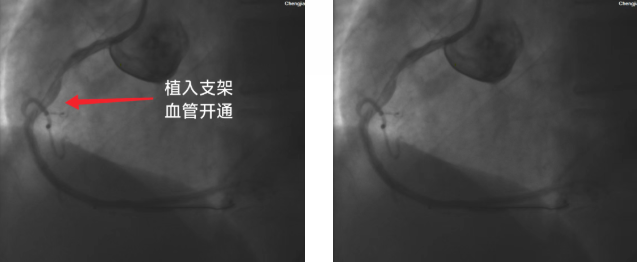

(植入支架后血管开通)

术中冠脉造影检查显示,患者右冠状动脉(RCA)中段完全闭塞,这正是引发急性心梗的核心病因。手术团队凭借丰富的临床经验和精湛的操作技术,迅速开展导丝通过、球囊扩张及支架植入等一系列操作,整个过程精准高效、有条不紊。18:42导丝顺利通过闭塞血管,血管成功开通,胸痛症状当即得到缓解。